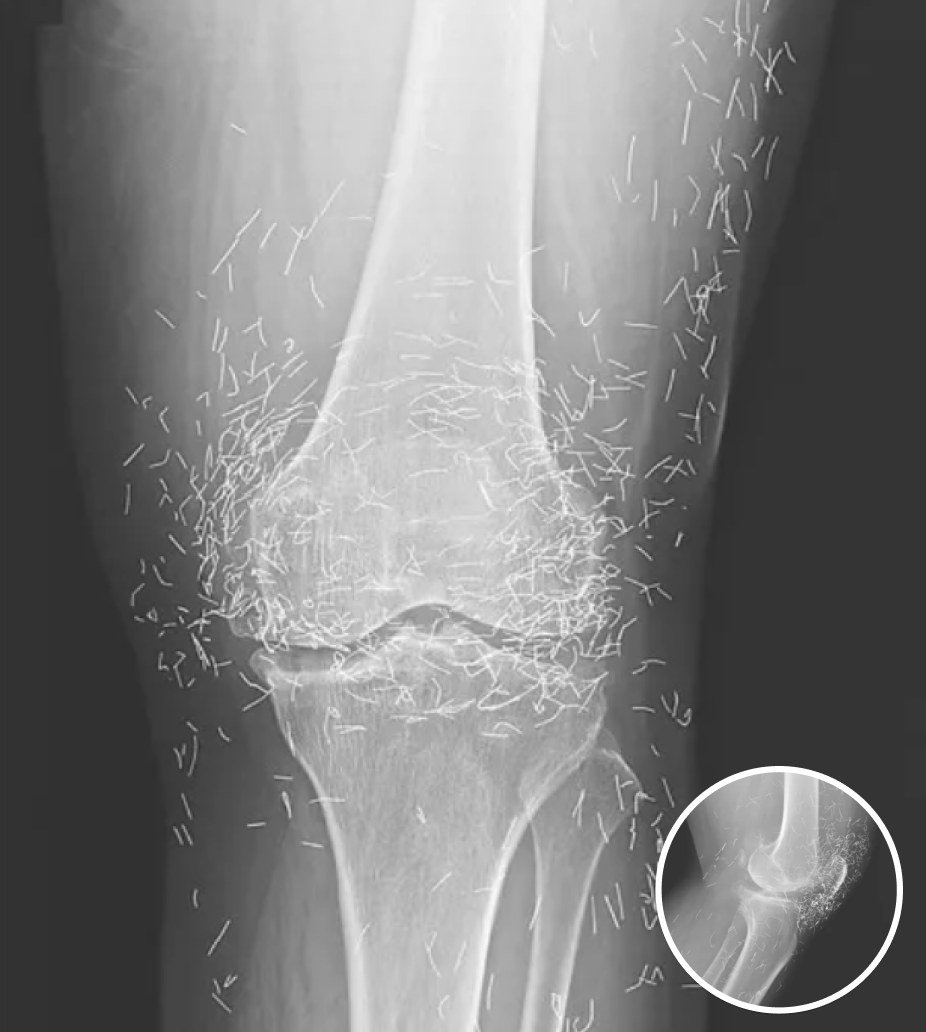

A 65-year-old woman from South Korea went to doctors for severe joint pain, and her X-ray ended up showing something very strange. The scan revealed hundreds of small gold needles left inside her knee tissue, and it stunned the medical team who looked at it.

Acupuncture uses thin needles placed in certain points on the body to ease pain. In her case the doctors said the gold needles were left inside on purpose, the idea being to give constant stimulation to the painful area.

There are more dangers too. If needles stay in the tissue they can block medical scans. The doctor also said: “They can obscure parts of the anatomy on an X ray.” He added that if a patient with metal fragments ever has an MRI, the magnets could make the pieces move and maybe even cut blood vessels.

The procedure has even gained a smaller following in the United States, with millions trying acupuncture for relief. The case of this woman was written up in the New England Journal of Medicine as a warning that sometimes these extreme treatments can go too far.